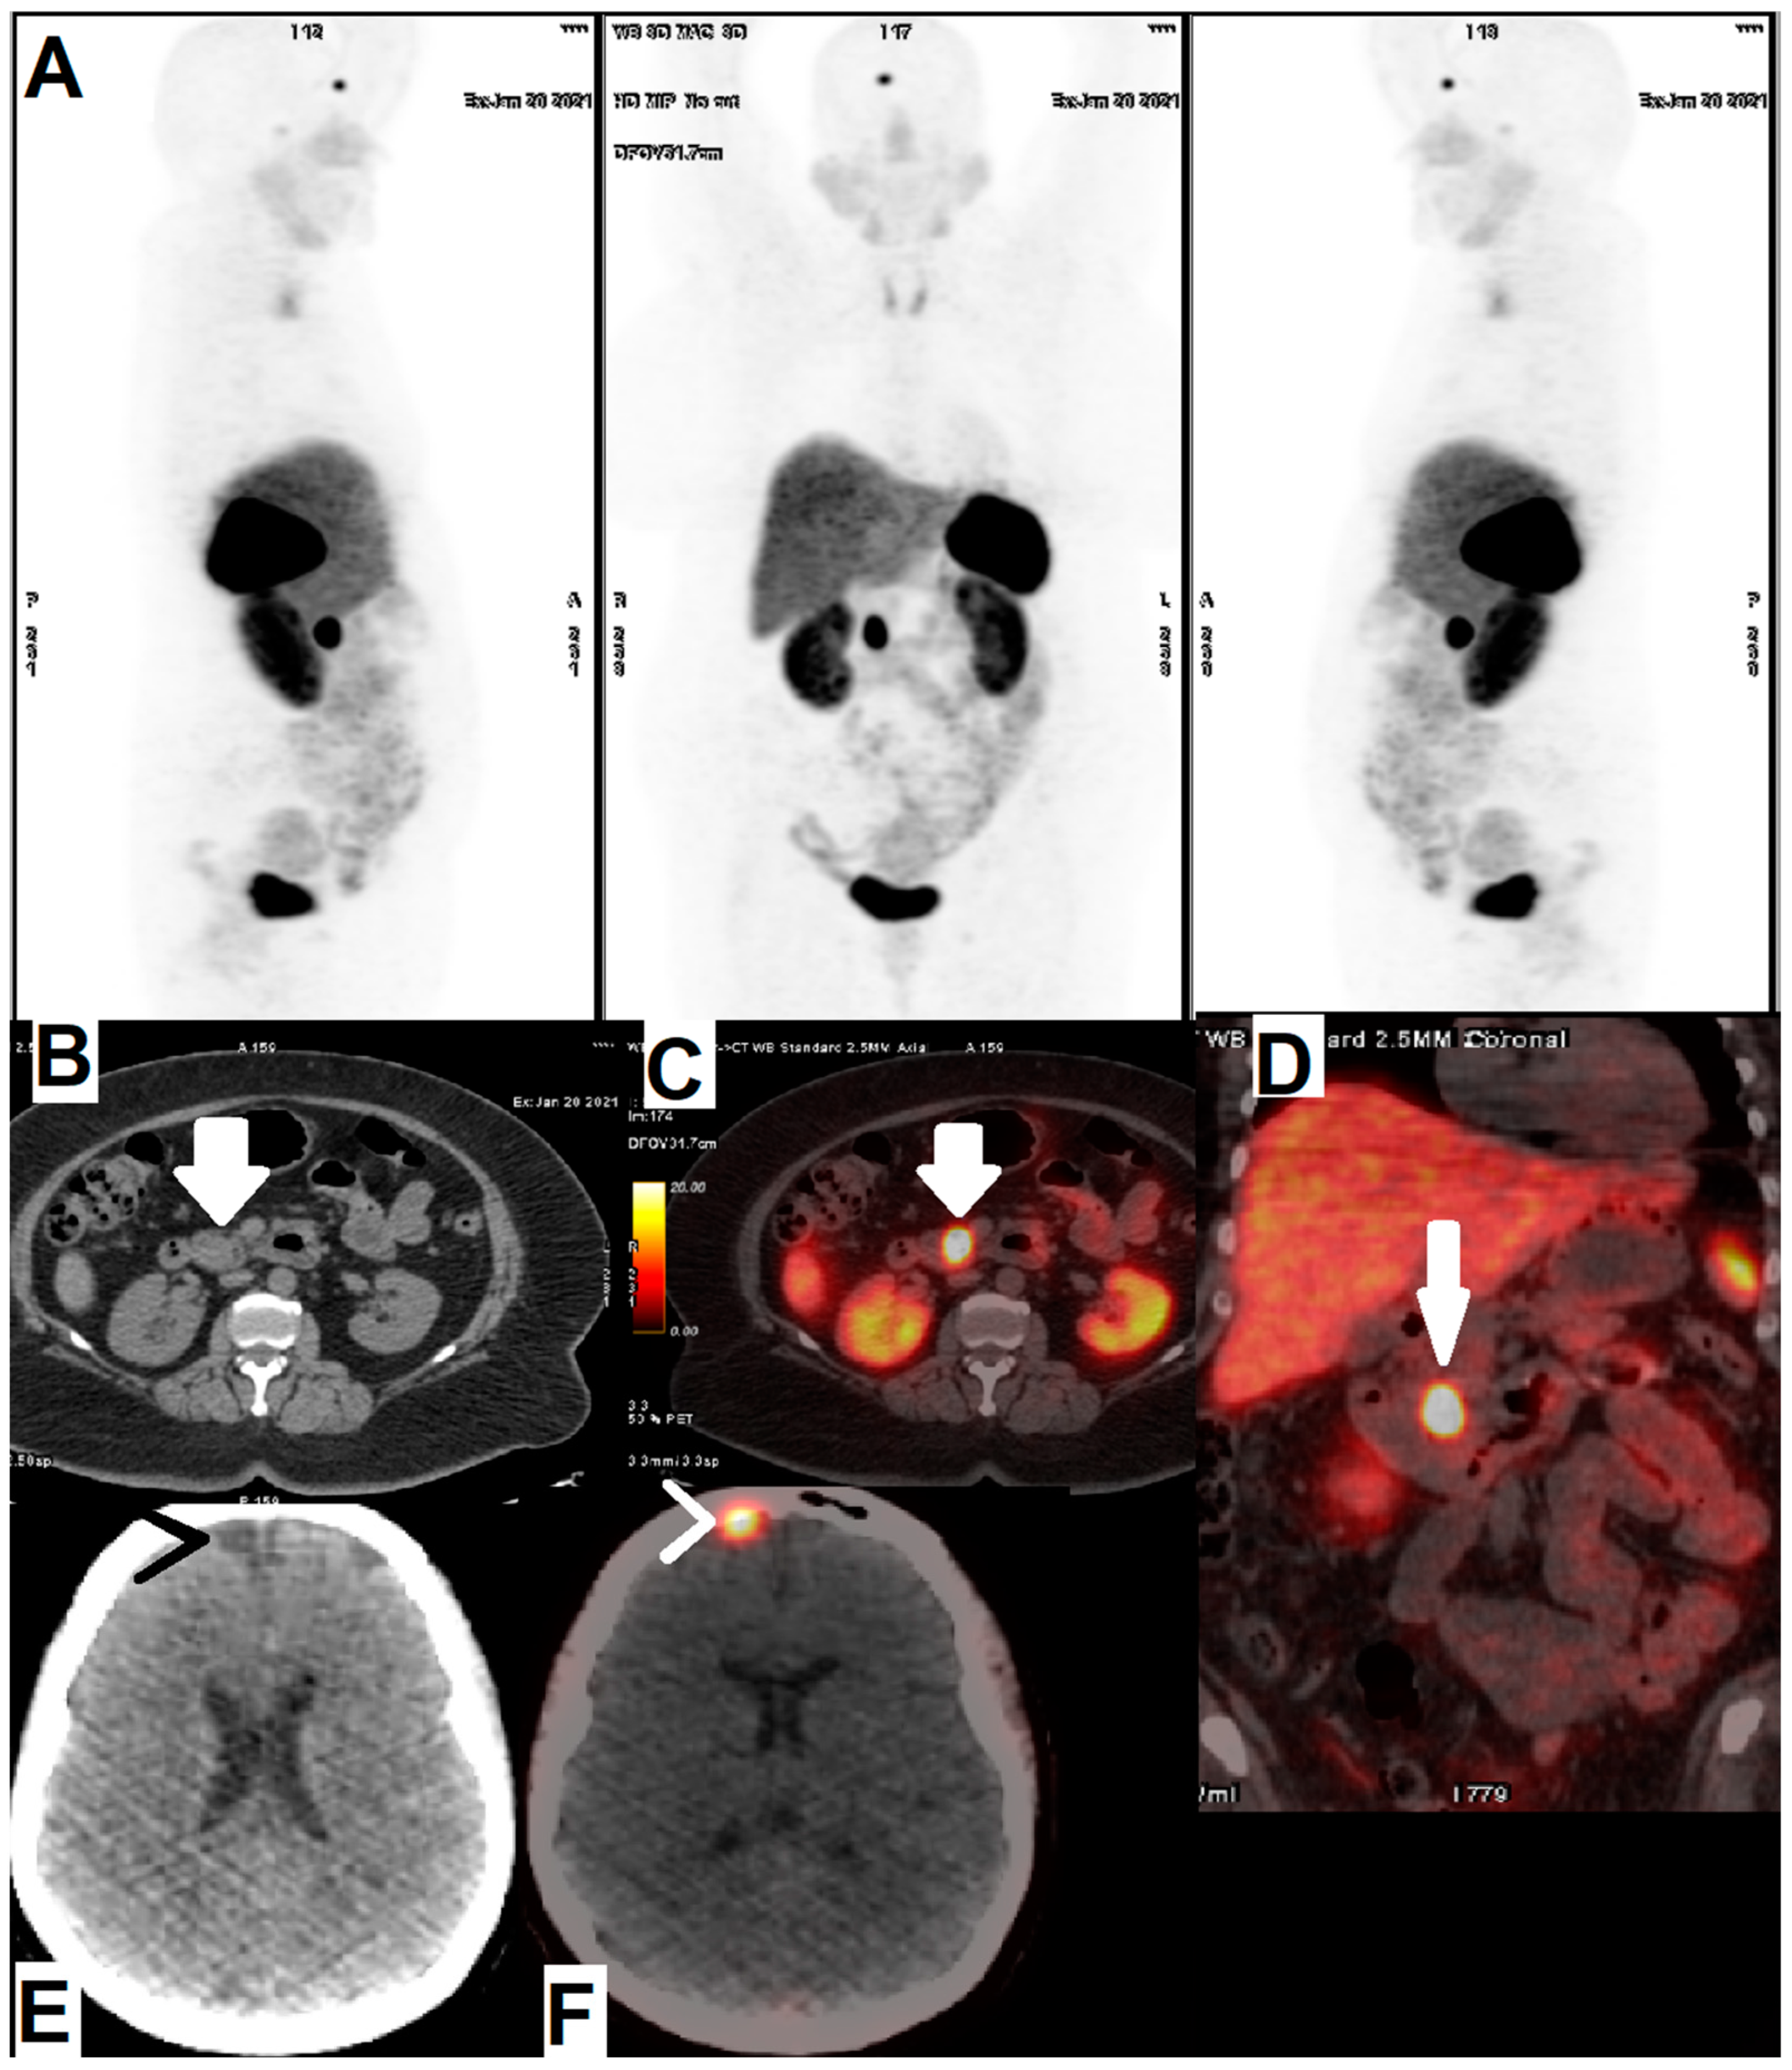

- Mirzaei, S.; Revheim, M.-E.; Raynor, W.; Zehetner, W.; Knoll, P.; Zandieh, S.; Alavi, A. 64Cu-DOTATOC PET-CT in patients with neuroendocrine tumors. Oncol. Ther. 2020, 8, 125–131. [Google Scholar] [CrossRef]

| [64Cu]Cu-DOTA-TOC | NET | 33 | 2019 | High detection rate and high target to background ratio in images raised [64Cu]Cu- DOTA-TATE as a promising and safe radiolabeled SST derivative for NET detection | [22] |